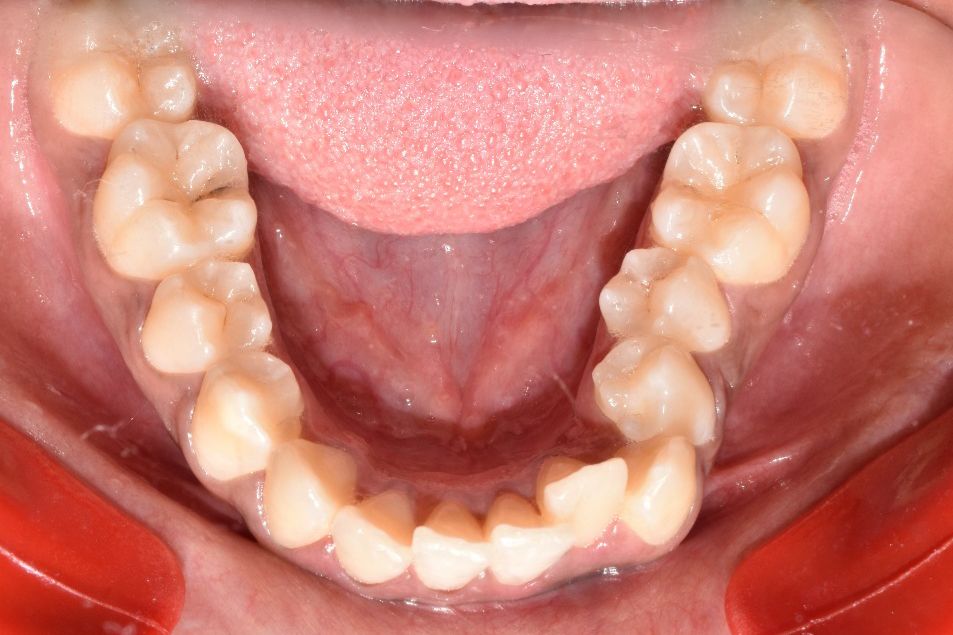

Before & After Results

At Aline Dent, we take pride in delivering visible and lasting improvements in our patients’ smiles. Our before-and-after results highlight the effectiveness of modern dental treatments combined with personalized care. This gallery showcases real dental cases treated at our clinic, giving you a clear idea of how different dental concerns can be corrected with the right treatment approach.

From minor corrections to complete smile enhancements, these teeth transformation results demonstrate how professional dental care can improve both oral health and appearance. Our experienced dental team carefully evaluates each patient’s needs and creates customized treatment plans to achieve natural, healthy, and confident smiles.

In this gallery, you will find a variety of smile makeover cases, including treatments for crooked teeth, gaps, discoloration, damaged teeth, and other common dental concerns.